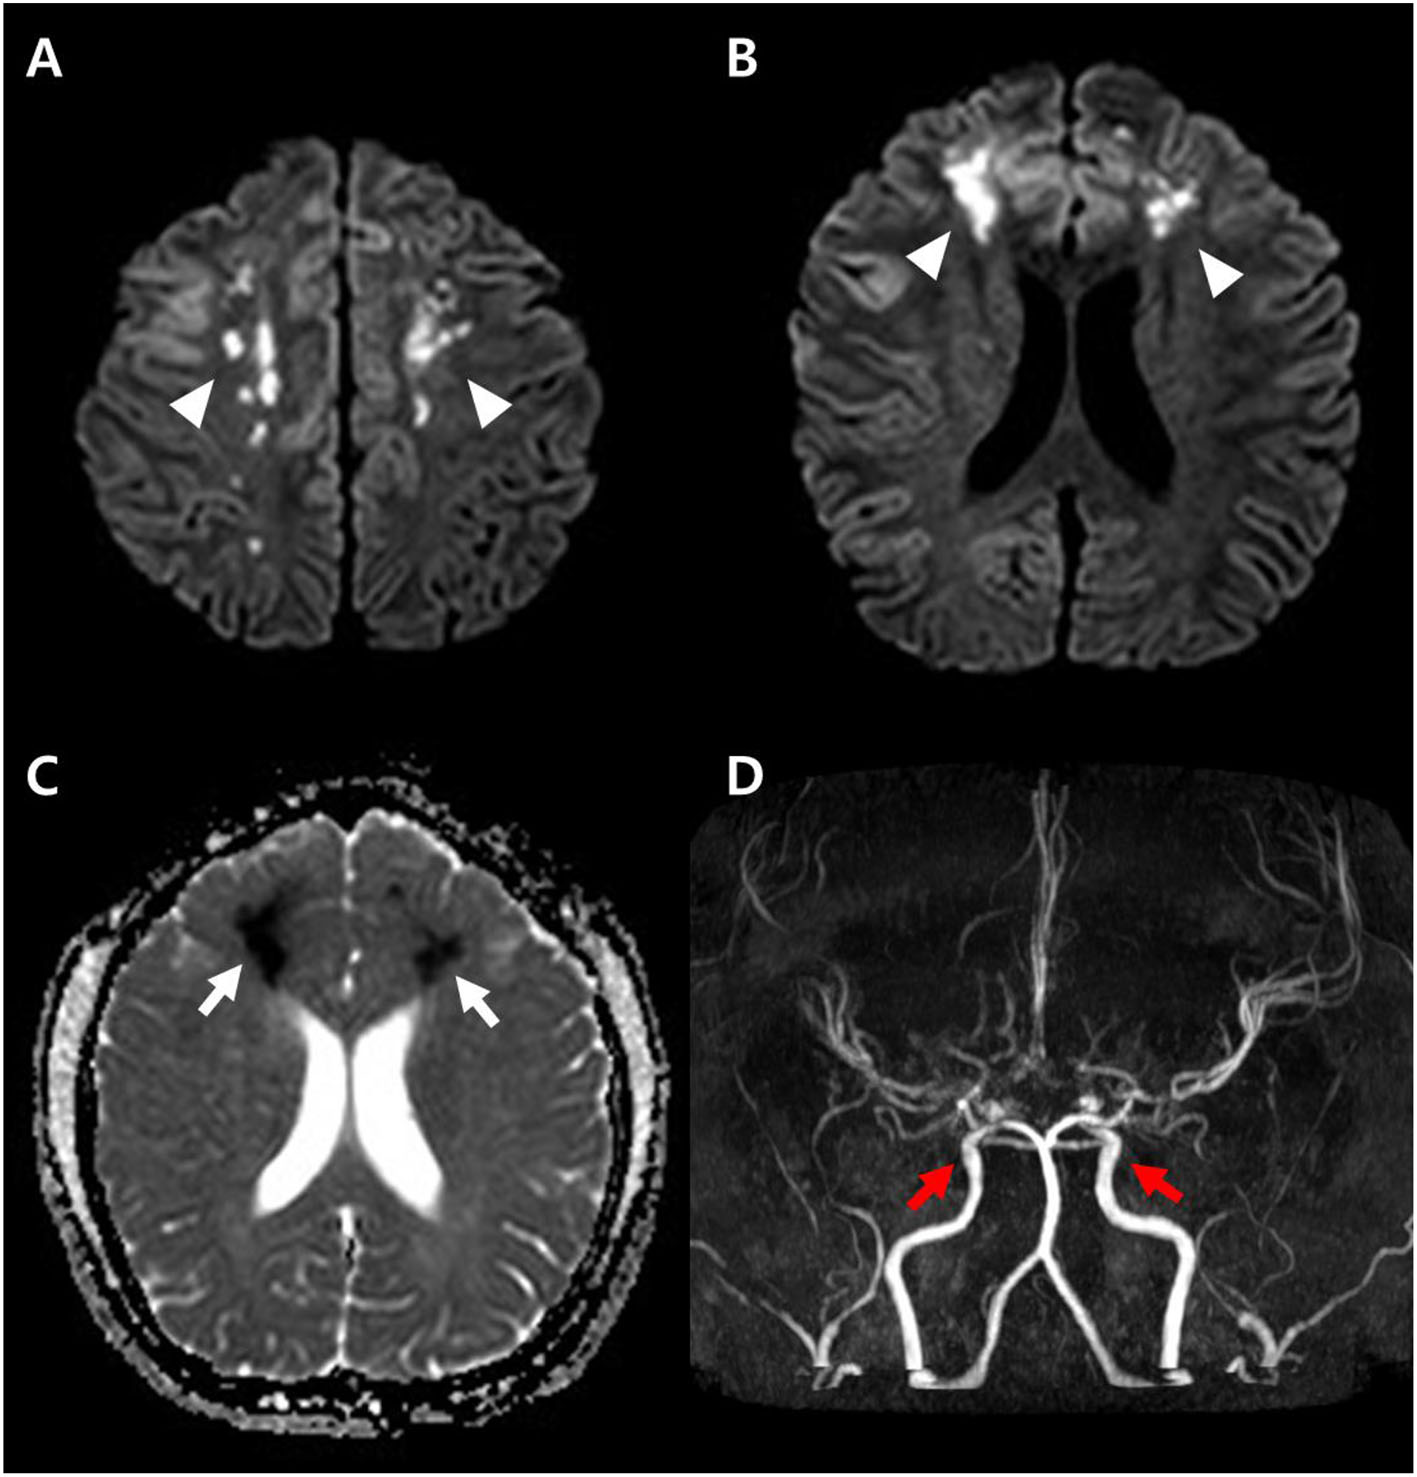

She was transferred to Samsung Medical Center with continuous alteration of mental status after the second seizure on the 12th day of hospitalization. On admission to this hospital, she was drowsy and sometimes confused. The patient consistently complained of severe headache. On the second hospitalization day, sudden weakness affecting both legs and dysarthria appeared. The symptoms waxed and waned during the day. On the third hospitalization day, her symptoms progressed into paraplegia and aphasia. Upon neurological examination, the Babinski sign and ankle clonus were positive bilaterally. The brain MRI on the day of transfer showed acute hemorrhage around the distal internal carotid artery (ICA) and right middle cerebral artery (MCA) obliterating the basal cistern and narrowing of both distal ICA and aneurysm at the left distal ICA (Figure 1). The brain MRI and magnetic resonance angiography (MRA) on the third hospital day demonstrated diffuse narrowing of bilateral MCAs, anterior cerebral arteries (ACAs), and distal ICAs, as well as small aneurysms at both distal ICAs (Figure 2D). In addition to the persistent SAH in the basal cistern and prepontine cistern, multifocal parasagittal acute infarctions were found (Figures 2A–C). Those findings raised the possibility of diffuse vasospasm associated with the SAH resulted from aneurysm rupture. The vessel wall MRI showed no contrast enhancement in the arterial wall, which could exclude the cerebral angiitis. Transfemoral cerebral angiography (TFCA) was performed on the sixth hospitalization day, revealing three unruptured aneurysms in both anterior choroidal arteries and left MCA and posthemorrhagic vasospasm involving both distal ICAs, MCAs, and ACAs (Figures 3A,F). The degree of narrowing of these cerebral blood vessels was severe for considering the endovascular coil embolization of the aneurysms. Therefore, we administered nimodipine and provided sufficient intravenous hydration to expand the vessels. On the seventh hospitalization day, after confirming that the vessels were widened enough to perform the intervention, we executed the first endovascular coil embolization for obliteration of unruptured aneurysms on the right anterior choroidal artery (Figures 3B–E). The upper motor neuron sign disappeared after the procedure. On the ninth hospitalization day, she became alert; however, the motor aphasia continued. She began to speak in sentences on the 15th day of hospitalization. On the seventeenth hospitalization day, we performed the second endovascular coil embolization for obliterating the left anterior choroidal artery aneurysm (Figures 3G–J). Although her brain MRI showed a slight reduction of infarction size compared to the previous results after the embolization, her clinical symptoms improved with the rehabilitation treatment. She was discharged on the forty-third hospitalization day without any motor deficit. The brain MRI and MRA performed 10 months after discharge demonstrated encephalomalacia in both parasagittal areas especially in the left frontal lobe (Figure 4). The electroencephalogram performed at that time showed epileptiform discharges in the left or right frontal areas. On her last follow-up in the outpatient clinic 14 months after discharge, her motor function was normal, and no neurologic deficit was observed.

Figure 4. Follow-up axial T2 weighted images (A) demonstrate the high signal intensity in both parasagittal areas suggesting the watershed injury (arrows). The MRA (B) shows improved narrowing of both MCAs and ACAs suggesting improved diffuse spasm of the arteries. There are remaining multifocal stenosis of the vessels at both distal internal carotid arteries, proximal middle cerebral arteries, and proximal anterior cerebral arteries.